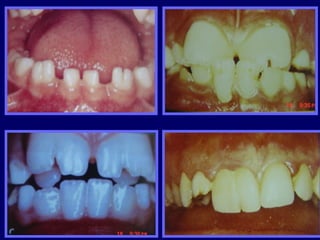

AMELOGENESIS IMPERFECTA

 Hipoplásico:

 Zonas ausentes de esmalte

 Afecta más a caras vestibulares

 Esmalte: blanco amarillento y marrón claro, consistencia dura,

fosas y surcos oscuras, delgado

 Hipocalcificado:

 Cualitativo

 Esmalte frágil, fácil de desprender

 Rx: falta de contacto entre dentina, esmalte

 Hipomaduro:

 Disminución en el contenido mineral

 Esmalte blando y rugoso, veteado de blanco a marrón (esmalte

en copos de nieve)

 Más frecuente en caras vestibulares y dientes superiores

AMELOGENESIS IMPERFECTA  Hipoplásico: Zonas ausentes de esmalte  Afecta más a caras vestibulares  Esmalte: blanco amarillento y marrón claro, consistencia dura, fosas y surcos oscuras, delgado  Hipocalcificado:  Cualitativo  Esmalte frágil, fácil de desprender  Rx: falta de contacto entre dentina, esmalte  Hipomaduro:  Disminución en el contenido mineral  Esmalte blando y rugoso, veteado de blanco a marrón (esmalte en copos de nieve)  Más frecuente en caras vestibulares y dientes superiores